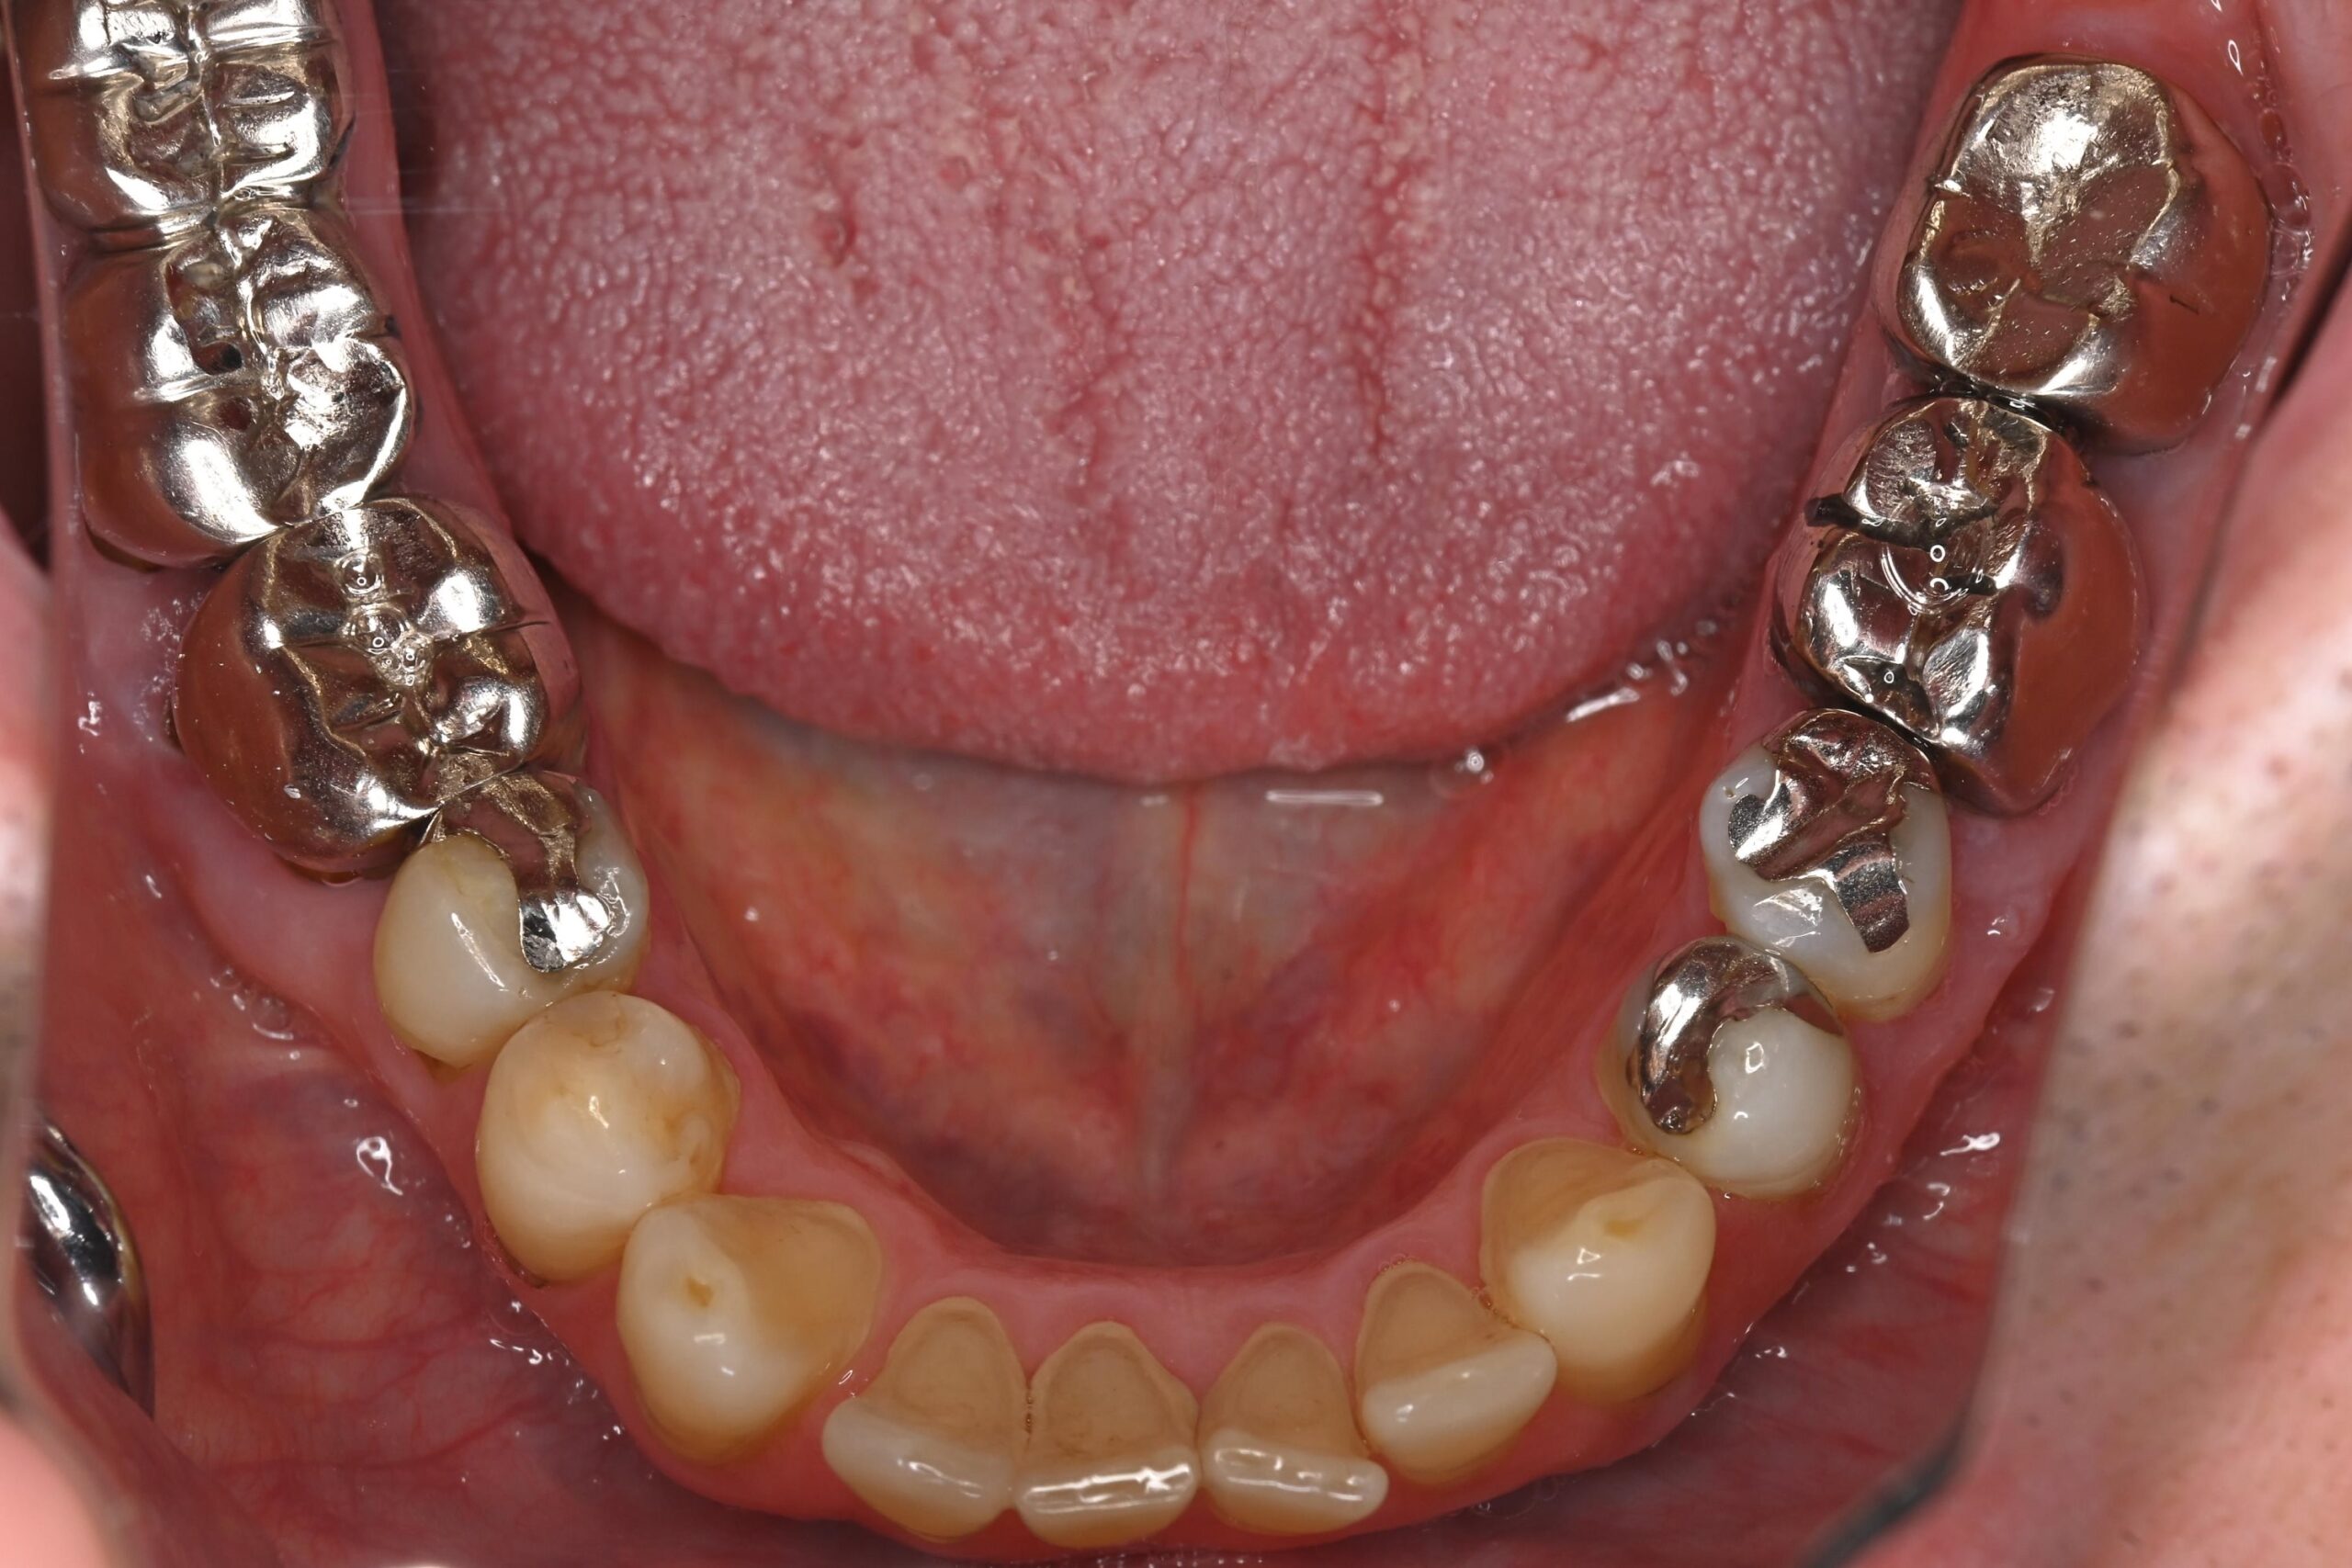

お口全体に虫歯や歯周病の原因となるプラーク(歯垢)が多く付着していました。右上奥歯は重度の虫歯で歯冠部(歯の頭)が失われており、左下奥歯は過去の治療箇所から細菌が入り込み、根の先に炎症が起きている状態でした。

患者様と相談の結果、期間や費用の面から矯正治療は行わず、「現在の噛み合わせを整えながら、金属をセラミックへやり替える治療」を選択しました。

セラミックを作製する前に全体的なトーンアップを行い、基準となる色を作りました。 - 審美修復(セラミック治療):

前歯の虫歯治療と、奥歯の古い金属をセラミックへ交換しました。 - 噛み合わせの調整:

切端咬合による噛み合わせの負担を考慮し、補綴材料としてジルコニアを選択しました。

ジルコニアは非常に高い強度と耐久性を持つ素材で、強い咬合力がかかる症例においても破折リスクを抑えやすい特性があります。 - 「色」へのこだわり:

銀歯をすべてセラミックへ置き換え、あわせてホワイトニングを行ったことで、口腔内全体が明るく清潔感のあるお口元になりました。また審美的な向上が得られただけでなく、プラーク(細菌)が付着しにくい環境を整えることができた点も大きな成果です。

Before